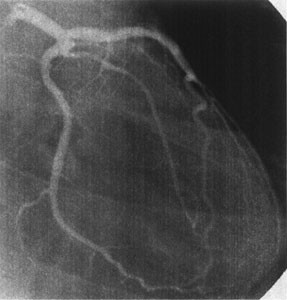

We report two young adult patients who had acute coronary syndrome after regression of coronary aneurysms caused by Kawasaki disease (KD). A 26 year-old man had acute anterior myocardial infarction at midnight after drinking alcohol. He had had bilateral coronary aneurysms caused by KD at the age of 8 months. Selective coronary angiograms (CAGs) at the age of 7 years revealed regression of both coronary aneurysms. He had no symptoms until the onset of acute myocardial infarction. The other patient was a 24 year-old man diagnosed as having a subendocardial infarction. He had had bilateral coronary aneurysms caused by KD at the age of 1 year. CAGs at the age of 9 years showed that both had regressed. It should be recognized that young adults with apparently normal coronary arteries angiographically after regression of large coronary aneurysms caused by KD may occasionally have acute coronary syndromes. We suspect intimal involvement of the coronary arterial wall after regression of the large aneurysms underlies the acute coronary syndrome in adults. Risk factors for atherosclerosis must be avoided in this population.

Fig. 1